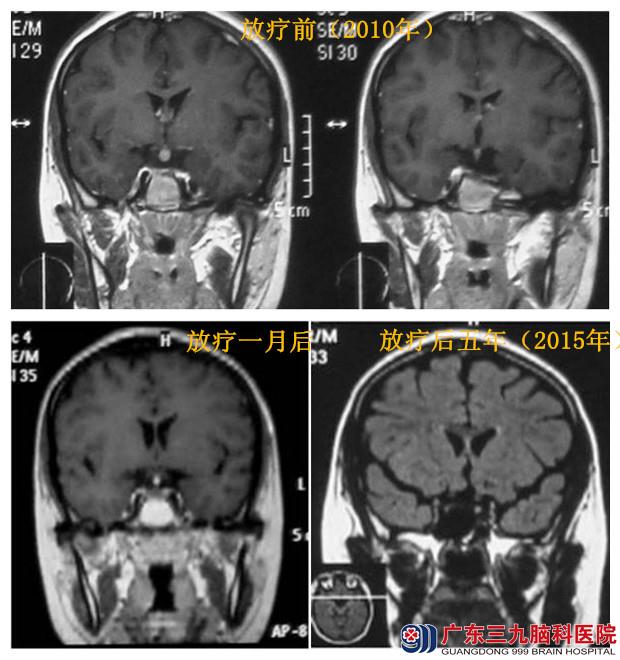

入院完善相关检查,肿瘤标记物HCG轻度增高,考虑生殖细胞瘤可能。因病灶部位位于垂体柄,手术可能导致内分泌紊乱及激素水平低下,患者及家属拒绝手术,选择行放疗治疗,诊断性适形放疗20Gy/10f后复查头颅MR,示垂体占位病变范围较前缩小,诊断:生殖细胞瘤。行全脑全中枢放疗3000cgy/15f,结束后复查头颅MR示病变已消失,随后行6程辅助化疗。患者随访至今已5年,未见肿瘤复发,未出现明显不良副反应,可正常工作与生活。